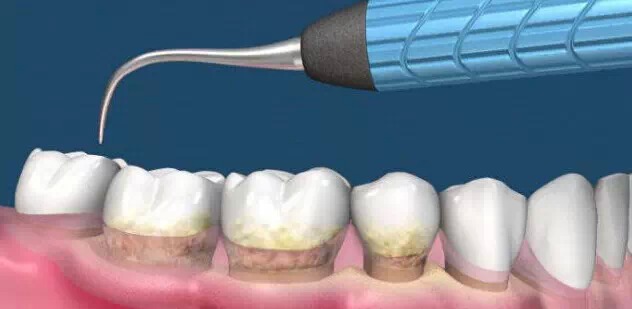

洗牙的确会给牙齿表面带来细微的划痕,但是这种划痕只在显微镜在可以看见,所以根本不用担心的哈。洗牙最主要的是消除牙结石,洁牙之后的抛光可以消除划痕,让牙齿表面更加光滑,大大减少牙结石和色素沉淀的附着。

平时我们吃饭、喝饮料等,都会使食物残渣残留在牙齿表面或者牙缝中,这些残渣单靠每天早晚刷牙是难以清除干净的,何况有些人还没有良好的口腔卫生习惯,久而久之细菌堆积就形成了牙结石、色素等顽固的牙垢。

牙垢是引发牙周病的主要原因,牙周病引起牙龈发炎、出血和口腔异味,严重时使患者的牙齿松动、移位甚至脱落,所谓“老掉牙”就是因牙周病引起的。